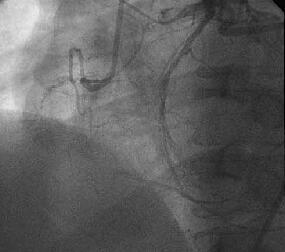

怱憻僇僥乕僥儖専嵏丗RCA偵嫹嶓昦曄傪擣傔傑偣傫偱偟偨偑丄LCx傊collateral傪

擣傔傑偟偨乮Figure1乯丅堷偒懕偄偰LCA偺憿塭傪帋傒傑偟偨偑丄JL僇僥乕僥儖偑

偳偆偟偰傕engage偱偒傑偣傫偱偟偨丅戝摦柆憿塭傪巤峴偟丄塃姤愲偺塃懁忋曽偵

憿塭嵻偺pooling傪擣傔傑偟偨乮Figure2乯丅擖岥晹偱姰慡暵嵡偟偰偄傞偲峫偊摨

晹埵偵懳偡傞僀儞僞乕儀儞僔儑儞傪巤峴偡傞偙偲偲偟傑偟偨丅擖岥晹偑塃懁忋曽

偵懚嵼偡傞偨傔丄僈僀僨傿儞僌僇僥乕僥儖偼丄JR僇僥乕僥儖傪巊梡偟傑偟偨

乮Figure3乯丅